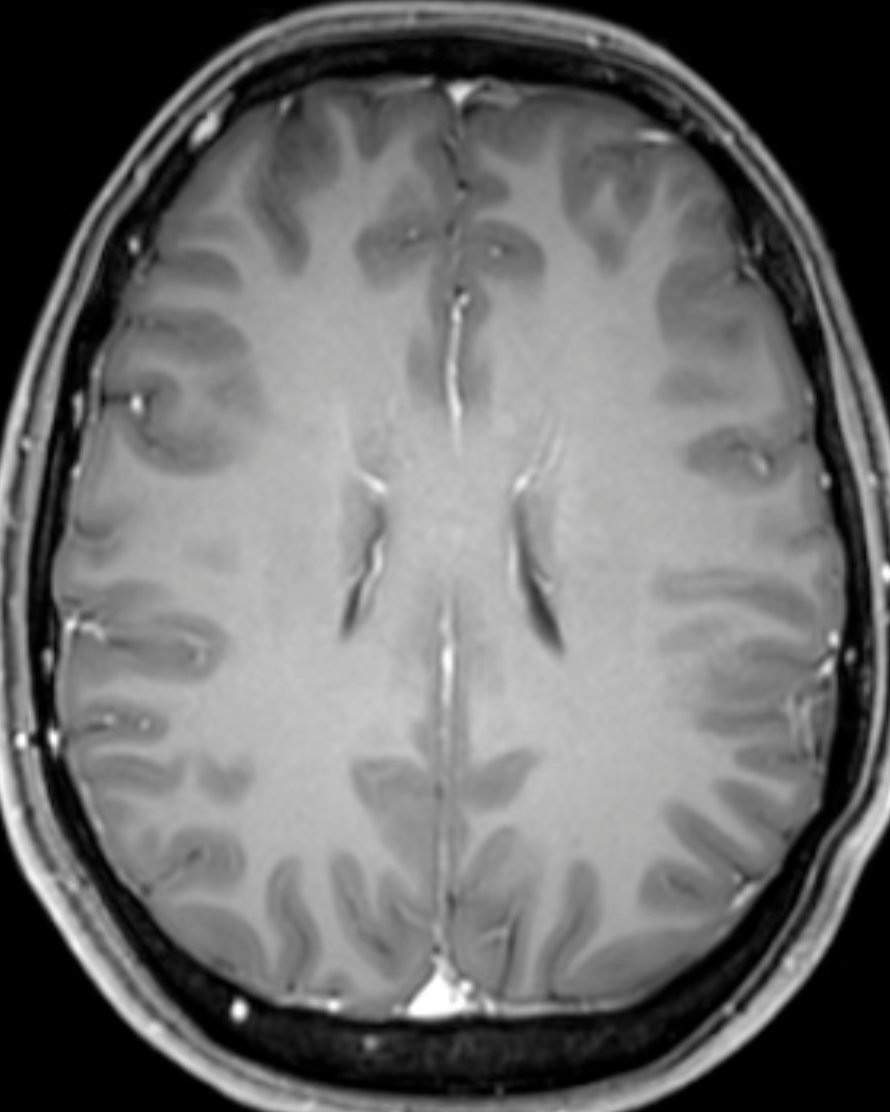

Trigger finger and palmar fibromatosis. Most palmar fibromas have a significant intimate association with the A1 pulley, and presence of trigger finger with adjacent palmar fibroma can exist and is important for hand surgeons to know preoperatively onlinelibrary.wiley.com/doi/10.1002/ju…